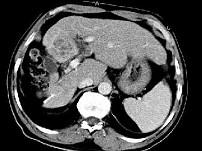

问题 女性,56岁,腹胀、双下肢浮肿、乏力、食欲不振,影像所见如下图,最佳的诊断是()

选项 A.酒精性肝硬化并肝血管瘤 B.血吸虫肝硬化并肝癌 C.肝炎后肝硬化并肝癌 D.局限性脂肪肝 E.原发性肝癌

答案 B